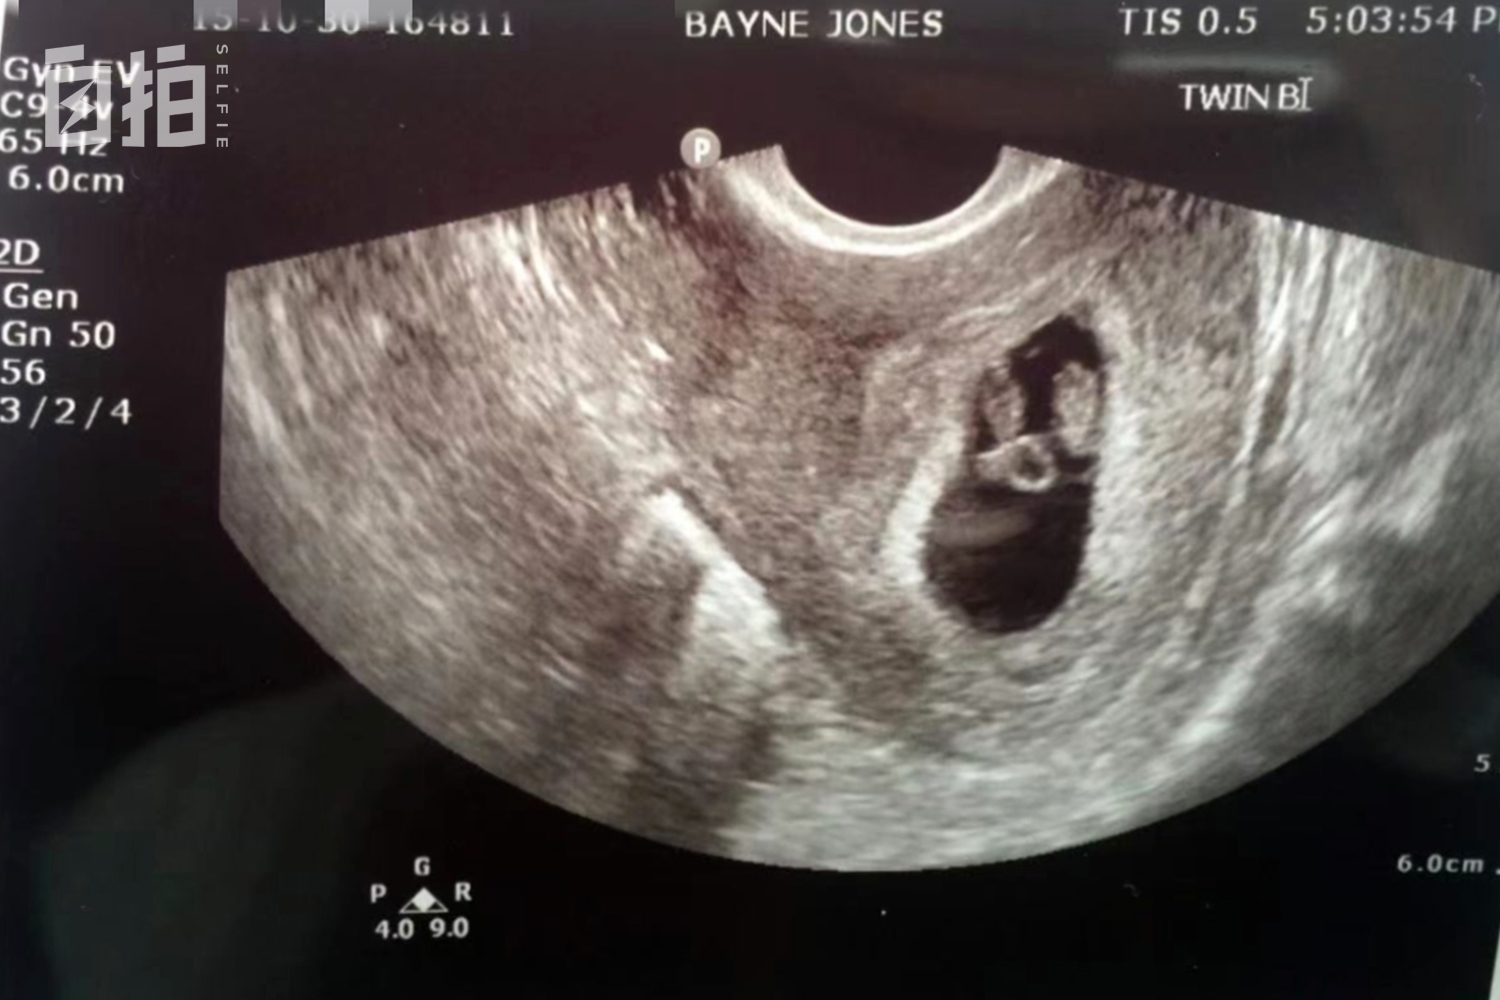

做生意三四年之后,我怀孕了。因为怀的是双胞胎,又有早产症状,医生建议卧床休息,我的店只能请人轮班。

我的双胞胎宝宝。

2016年4月,我们两个孩子出生,哥哥1260克,弟弟只有990克,非常瘦弱。生孩子第一年,我们有大半年时间都是在医院度过的。小儿子器官发育不好,心脏、呼吸系统、眼睛、耳朵……各种器官都需要定期检查,还需要成天吸氧。

小儿子出生才不到两斤,非常瘦弱。